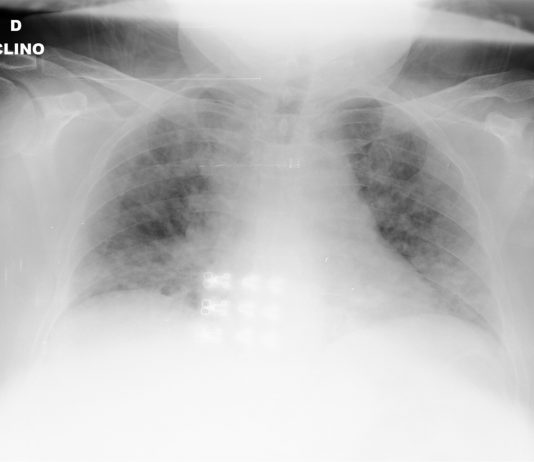

R. Bonacini, G. Besutti, P. PattaciniRadiologia IRCCS Reggio Emilia; Direttore Pierpaolo Pattacini

68-year-old male

with fever, dyspnea and diarrhea for 7 days. Blood test: leukocytosis, increased C-PR, procalcitonin in

the range. Medical history: chronic lymphocytic leukemia under follow-up,

dyslipidemia and HTA.

Chest radiography: